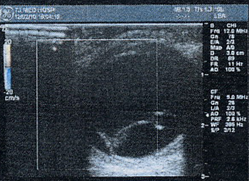

图2 B超:右眼视网膜脱离,脉络膜脱离?

Fig 2 B- scan showed retinal detachment in the right eye, and choroidal detachment was suspected in the temporal-superior part.

图3 CDI:右眼玻璃体腔内可见Y形底端与视乳头相连隆起条索,其内可见红蓝色血流信号。颞上方可见半圆形隆起,基底宽20.75px,高12px,边界清楚,内部无回声,未探及红蓝血流信号及能量信号,隆起表面可见血流信号,与后极部隆起在基底后缘相连。

Fig3 CDI showed a Y-shapedstrip with rich blood supply connecting to the optic papilla. In the temporal region. There was a semicircular bulge with a base of 20.75px×12px.Blood flow signals were not visible on the surface of the bulge, and was continuous with the uplift of the posterior pole at the base margin.

图4 UBM:前方中央深度1.94mm,全周小梁虹膜夹角开放,全周睫状体水肿脱离,颞上方睫状体见较大囊腔,内无回声.

Fig 4 UBM showed circumferential ciliary body edema and a localized ciliary cyst in the temporal-superior part. No echo sound was detected inthe cavity.